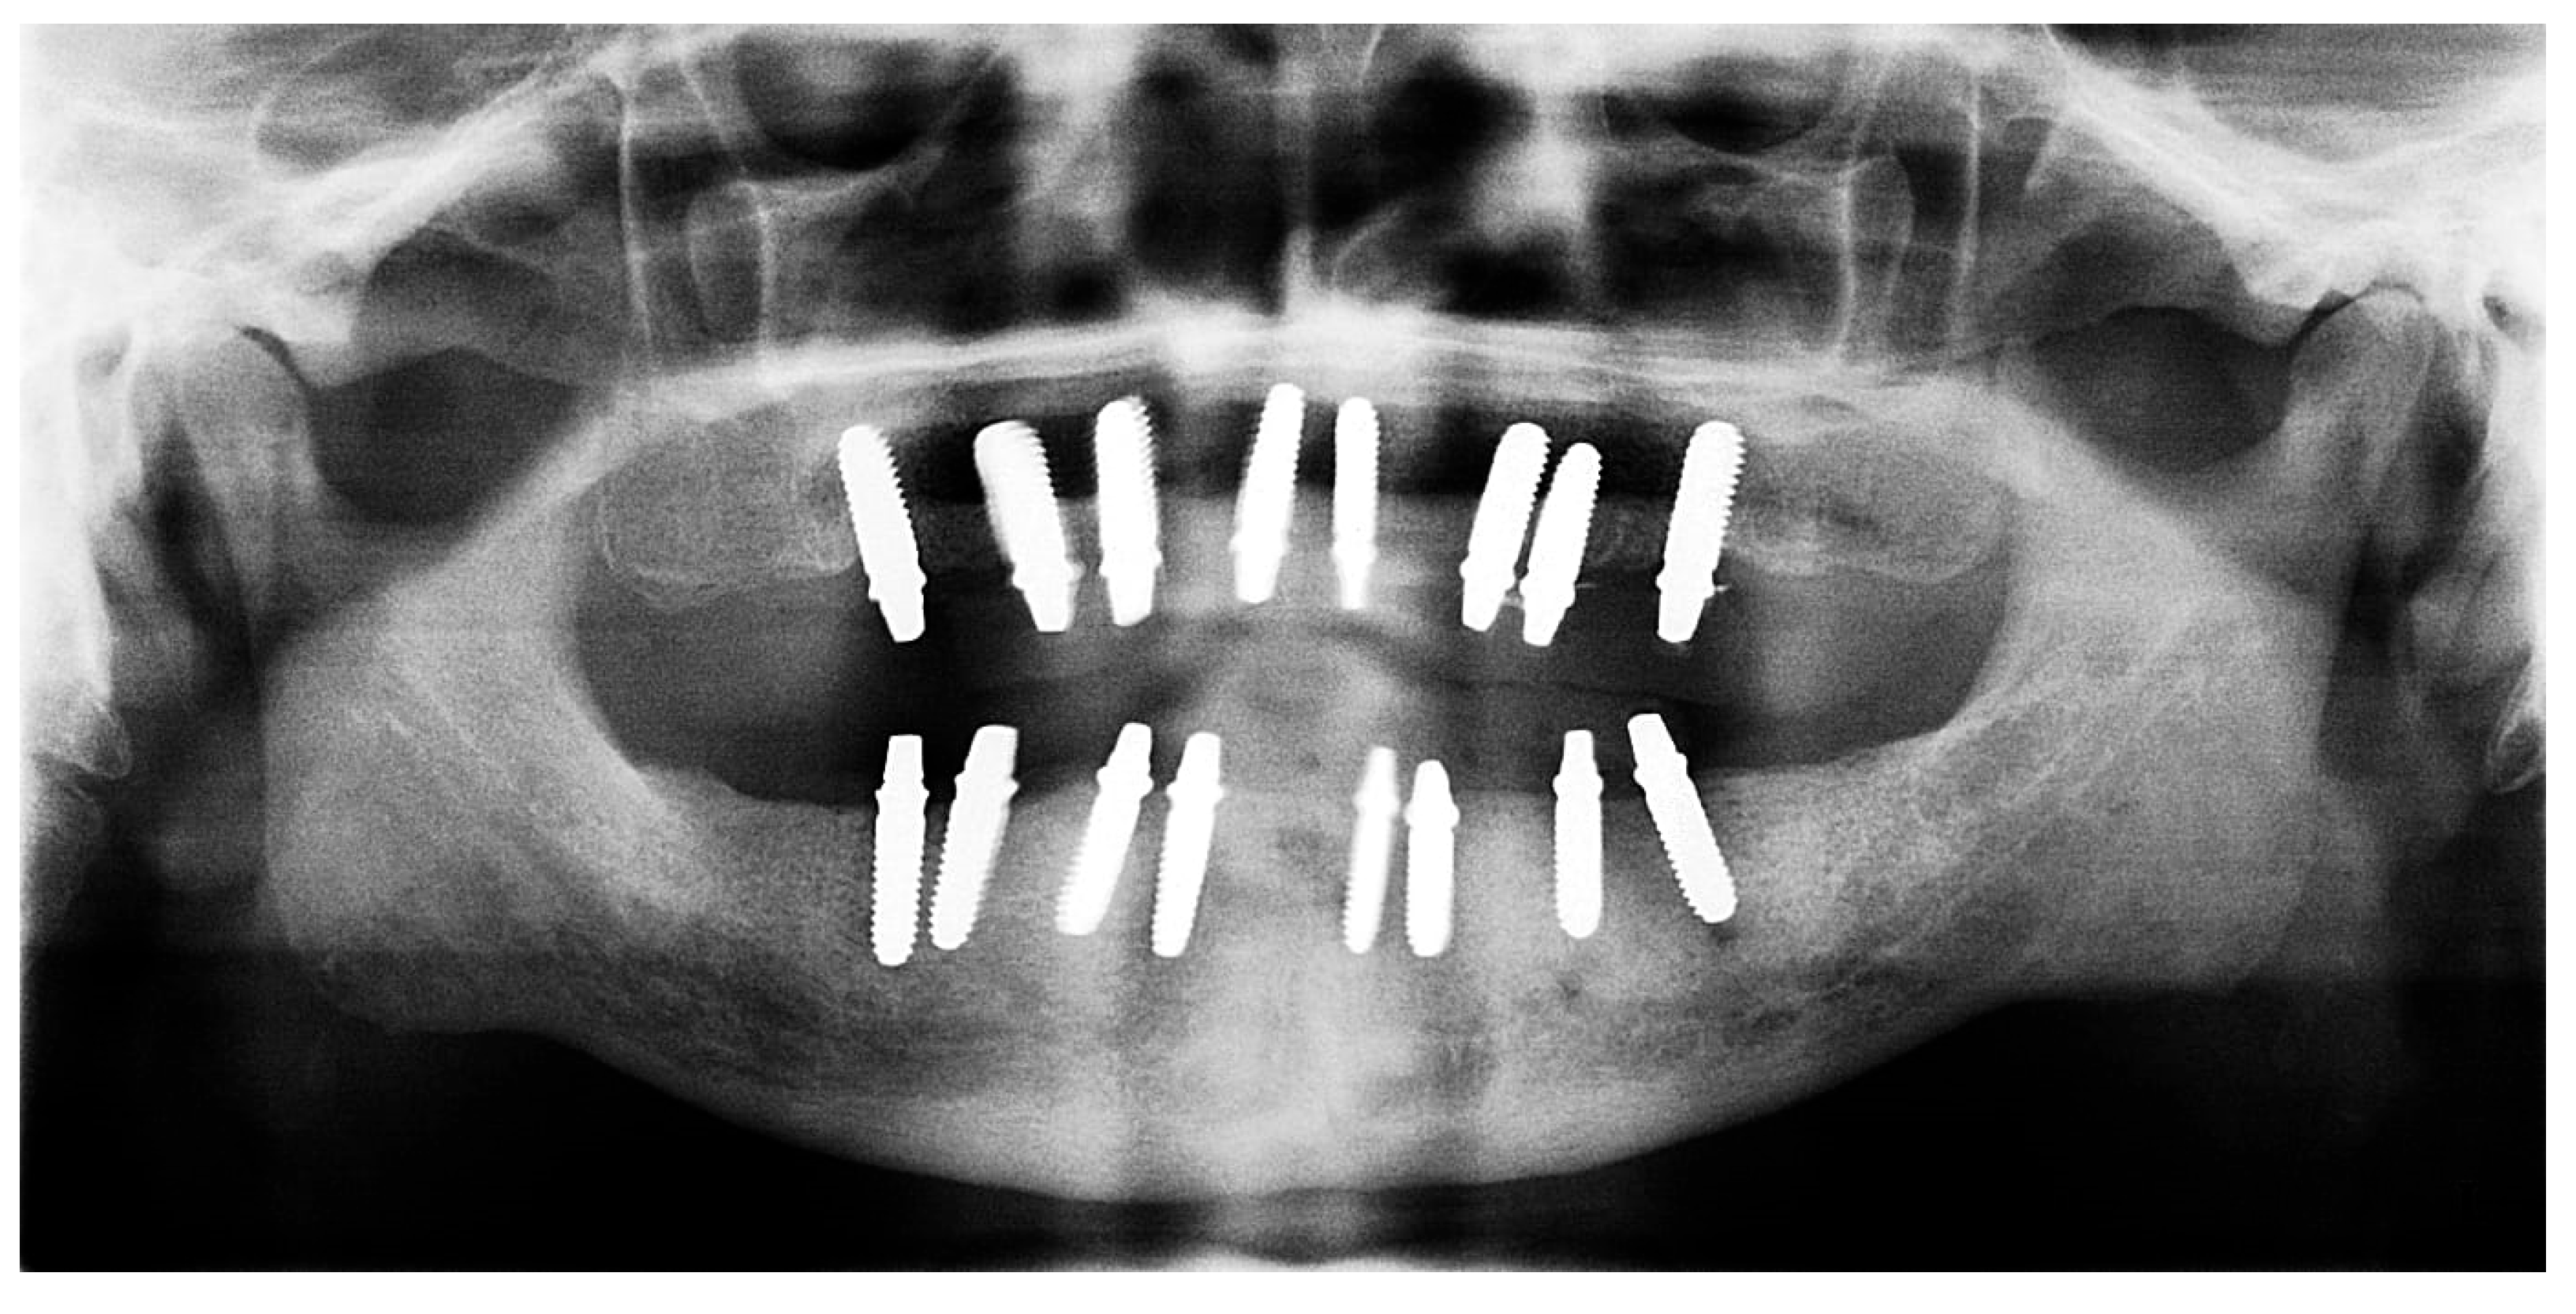

Figure 13. Panoramic X-ray showing the inserted dental implants (taken 10 October 2022).

Each telescopic crown was sandblasted on the internal surfaces, then placed in an ultrasonic bath and treated with the manufacturer-specified “Bredent” solution. A resin cement was utilized to bond each telescopic crown to its respective zirconia abutment. The arches were scanned once again and sent to the lab for the fabrication of segmented zirconia bridges, which were subsequently provisionalized with PEEK crowns (Figure 11, Figure 12 and Figure 13).

Radiographic evaluation in this study was limited to qualitative and linear assessment of crestal bone stability. While X-rays provide reliable detection of changes in marginal bone level, they cannot quantify bone mineral density (BMD). Hence, the radiographs presented here serve as indicators of implant stability rather than bone density evaluation. Quantitative assessment of bone density would require modalities such as CBCT voxel analysis or dual-energy X-ray absorptiometry (DEXA), which were not part of this retrospective case.